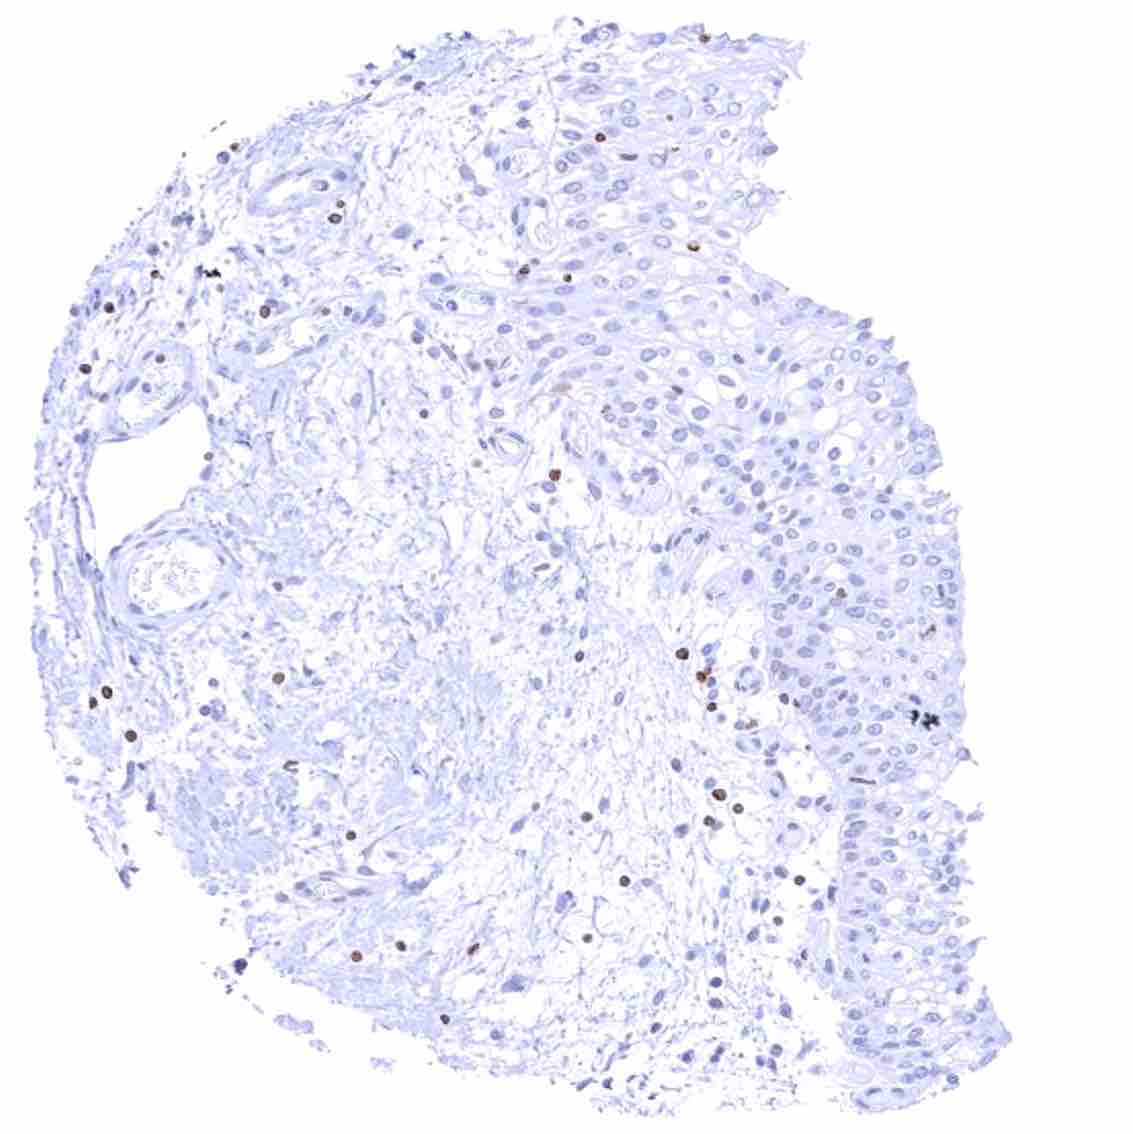

Prostate – Weak to moderate bcl-2 staining of a fraction of basal cells.